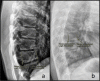

Early recognition of osteoporosis in children and adolescents is important in order to establish an appropriate diagnosis of the underlying condition and to initiate treatment if necessary. In this review, we present the diagnostic work-up, and its pitfalls, of pediatric patients suspected of osteoporosis including a careful collection of the medical and personal history, a complete physical examination, biochemical data, molecular genetics, and imaging techniques. The most recent and relevant literature has been reviewed to offer a broad overview on the topic. Genetic and acquired pediatric bone disorders are relatively common and cause substantial morbidity. In recent years, there has been significant progress in the understanding of the genetic and molecular mechanistic basis of bone fragility and in the identification of acquired causes of osteoporosis in children. Specifically, drugs that can negatively impact bone health (e.g. steroids) and immobilization related to acute and chronic diseases (e.g. Duchenne muscular dystrophy) represent major risk factors for the development of secondary osteoporosis and therefore an indication to screen for bone mineral density and vertebral fractures. Long-term studies in children chronically treated with steroids have resulted in the development of systematic approaches to diagnose and manage pediatric osteoporosis.

Conclusions: Osteoporosis in children requires consultation with and/or referral to a pediatric bone specialist. This is particularly relevant since children possess the unique ability for spontaneous and medication-assisted recovery, including reshaping of vertebral fractures. As such, pediatricians have an opportunity to improve bone mass accrual and musculoskeletal health in osteoporotic children.